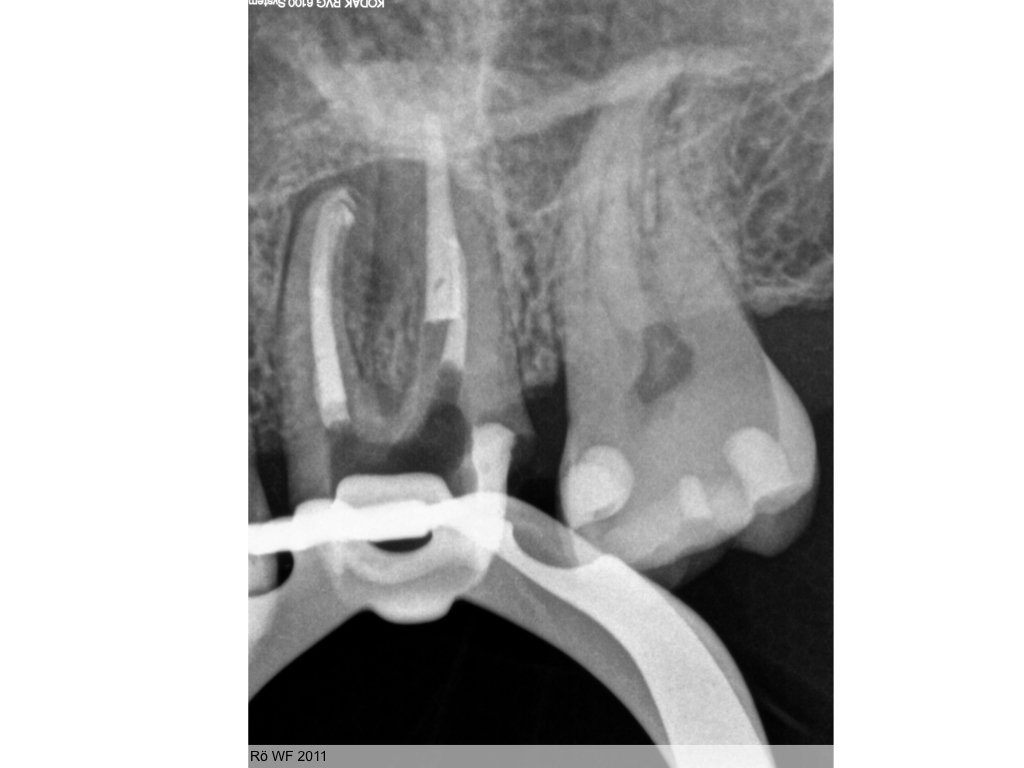

Heilung oder was?